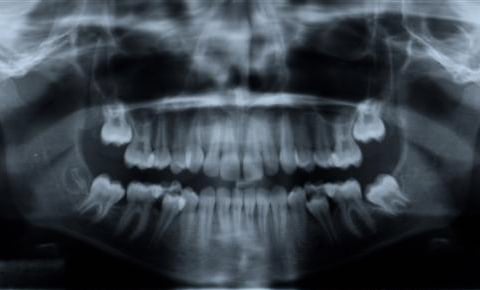

Digital Panoramic X-Rays

Panoramic x-rays offer patients a complete detailed image of the entire mouth including the teeth, jaw (upper and lower), sinuses, and TMJ.

It provides a complete picture on how everything looks and relates to each other.